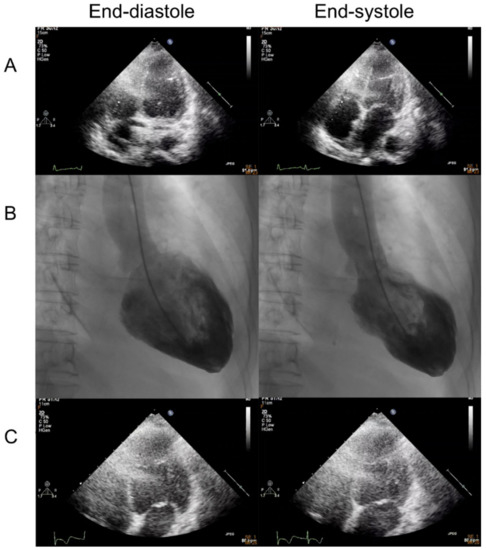

Cardiovascular events such as myocarditis following mRNA COVID-19 vaccination are increasing. We present a 67-year-old postmenopausal woman with Takotsubo Syndrome and Graves’ disease after mRNA COVID-19 vaccination. She developed chest pain and shortness of breath one week after vaccination. An electrocardiogram revealed ST [...] Read more.

Cardiovascular events such as myocarditis following mRNA COVID-19 vaccination are increasing. We present a 67-year-old postmenopausal woman with Takotsubo Syndrome and Graves’ disease after mRNA COVID-19 vaccination. She developed chest pain and shortness of breath one week after vaccination. An electrocardiogram revealed ST elevation in the precordial leads. Coronary angiography revealed the absence of obstructive coronary artery disease, and the left ventriculography showed a typical feature with apical ballooning. Laboratory workup showed the elevation of free T4 and thyrotropin receptor antibodies. It was presumed that Takotsubo Syndrome and Graves’ disease were probably related to the COVID-19 mRNA vaccination. The patient was treated with low-dose bisoprolol, diuretics, carbimazole, and steroid and discharged uneventfully. The mRNA COVID-19 vaccination is still safe and effective to defend against COVID-19 pandemic. However, clinicians should be aware of the possible cardiovascular adverse events other than myocarditis following vaccination. Full article